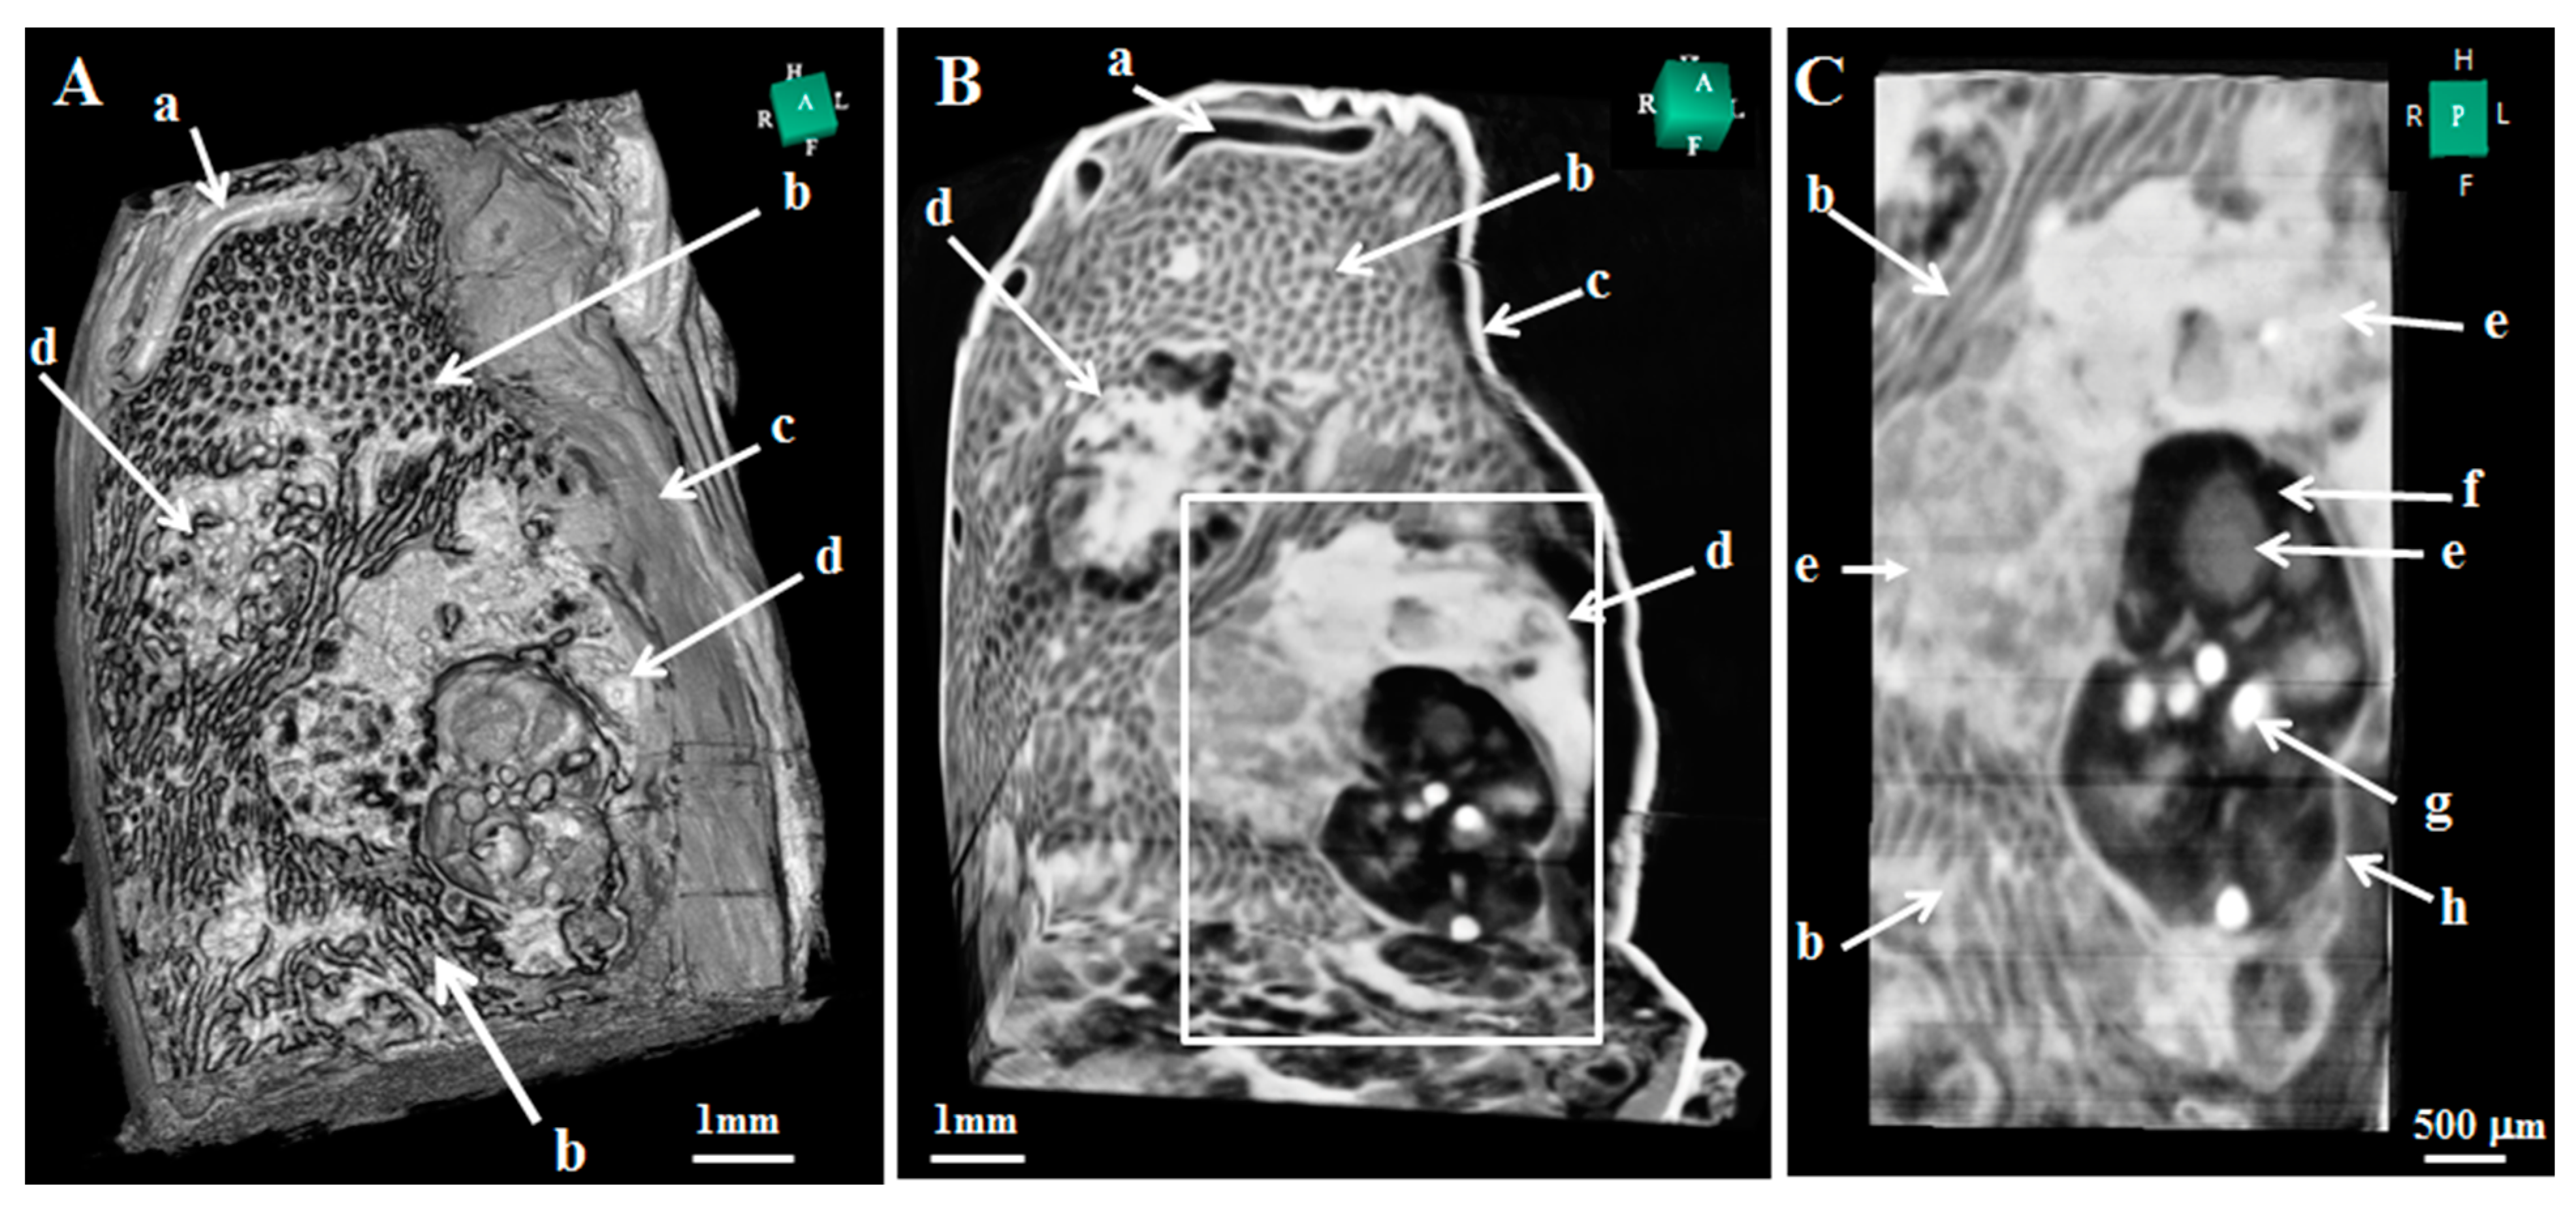

- Nohara, A.; Owaki, N.; Matsubayashi, J.; Katsube, M.; Imai, H.; Yoneyama, A.; Yamada, S.; Kanahashi, T.; Takakuwa, T. Morphometric analysis of secondary palate development in human embryos. J. Anat. 2022, 241, 1287–1302. [Google Scholar] [CrossRef] [PubMed]

- Osaka, M.; Ishikawa, A.; Yamada, S.; Uwabe, C.; Imai, H.; Matsuda, T.; Yoneyama, A.; Takeda, T.; Takakuwa, T. Positional Changes of the Ocular Organs During Craniofacial Development. Anat. Rec. 2017, 300, 2107–2114. [Google Scholar] [CrossRef]

- Toyoda, S.; Shiraki, N.; Yamada, S.; Uwabe, C.; Imai, H.; Matsuda, T.; Yoneyama, A.; Takeda, T.; Takakuwa, T. Morphogenesis of the Inner Ear at Different Stages of Normal Human Development. Anat. Rec. 2015, 298, 2081–2090. [Google Scholar] [CrossRef]

- Suzuki, Y.; Matsubayashi, J.; Ji, X.; Yamada, S.; Yoneyama, A.; Imai, H.; Matsuda, T.; Aoyama, T.; Takakuwa, T. Morphogenesis of the femur at different stages of normal human development. PLoS ONE 2019, 14, e0221569. [Google Scholar] [CrossRef] [PubMed]

- Fujii, S.; Muranaka, T.; Matsubayashi, J.; Yamada, S.; Yoneyama, A.; Takakuwa, T. Bronchial tree of the human embryo: Categorization of the branching mode as monopodial and dipodial. PLoS ONE 2021, 16, e0245558. [Google Scholar] [CrossRef] [PubMed]

- Okuno, K.; Ishizu, K.; Matsubayashi, J.; Fujii, S.; Sakamoto, R.; Ishikawa, A.; Yamada, S.; Yoneyama, A.; Takakuwa, T. Rib Cage Morphogenesis in the Human Embryo: A Detailed Three-Dimensional Analysis. Anat. Rec. 2019, 302, 2211–2223. [Google Scholar] [CrossRef] [PubMed]